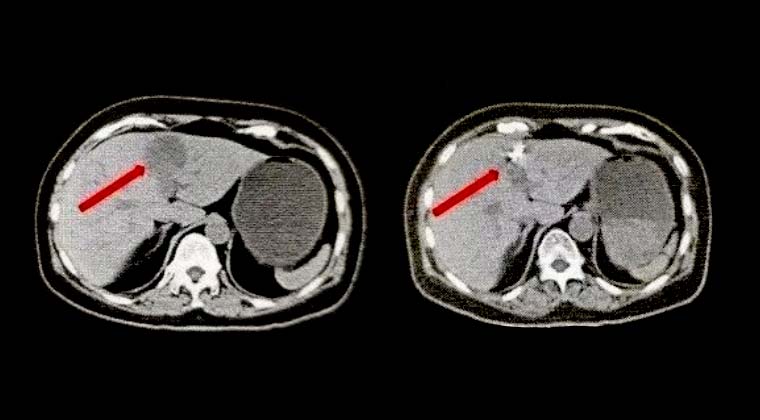

① Случай 1:

Пациентка: женщина, 58 лет, плоскоклеточный рак шейки матки

Пациентка обратилась в нашу больницу примерно через полмесяца после последнего курса химиотерапии из-за послеоперационного рецидива.

КТ показало вторичные злокачественные очаги в печени.

После консультации специалистов по онкологии было решено провести имплантацию частиц йод-125 в метастатические очаги печени.

Левая картинка: КТ до операции

Правая картинка: Через месяц после лечения, контрольная КТ (очаги опухоли явно исчезли)